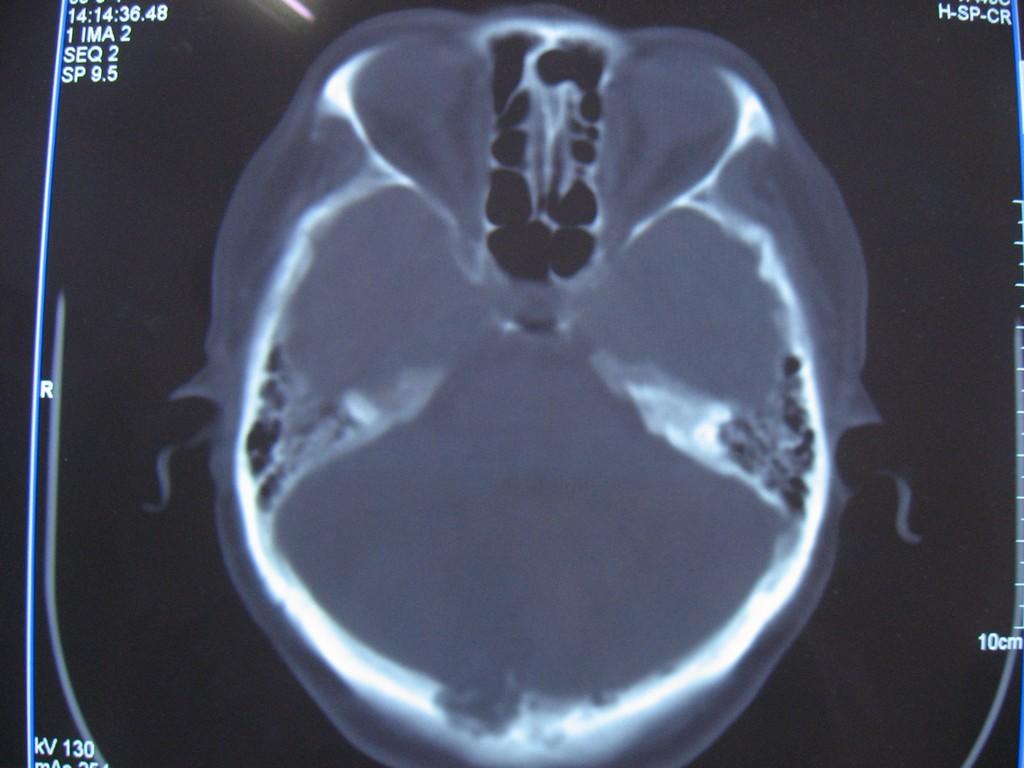

标题: CT22032B:枕骨破坏(从新调整窗宽窗位) [打印本页]

标题: CT22032B:枕骨破坏(从新调整窗宽窗位)

女性病人,53岁,偶尔感枕部针刺样疼痛,ct扫描如下。

蛛网膜颗粒压迹。鉴别:骨巨,嗜酸性肉芽肿,骨髓瘤。

蛛网膜颗粒压迹。

骨巨,嗜酸性肉芽肿,骨髓瘤,动脉瘤样骨囊肿可能

支持蛛网膜颗粒压迹。

支持蛛网膜颗粒压迹,鉴别:骨巨,嗜酸性肉芽肿,骨髓瘤、转移瘤

支持蛛网膜颗粒压迹,嗜酸性肉芽肿发生于30岁以下,基本排除,骨髓瘤、转移瘤多伴有软组织肿块,范围较广。

枕骨蛛网膜颗粒压迹。